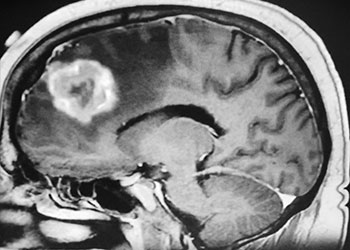

Brain:

Cerebral Metastases from Non-Small Cell Lung Cancer

Author: Xavier P. J. Gaudin D.O., F.A.C.O.S., Read More!